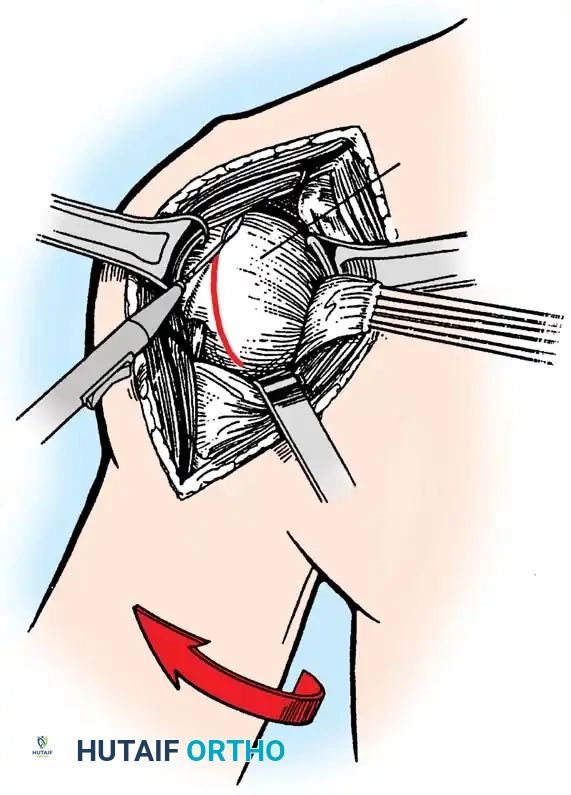

3. Humeral Head Resection

Dislocate the humeral head anteriorly through external rotation and extension. Remove peripheral osteophytes to identify the true anatomical neck. The humeral cut is made along the anatomical neck, typically at 30 degrees of retroversion and 45 degrees of inclination.